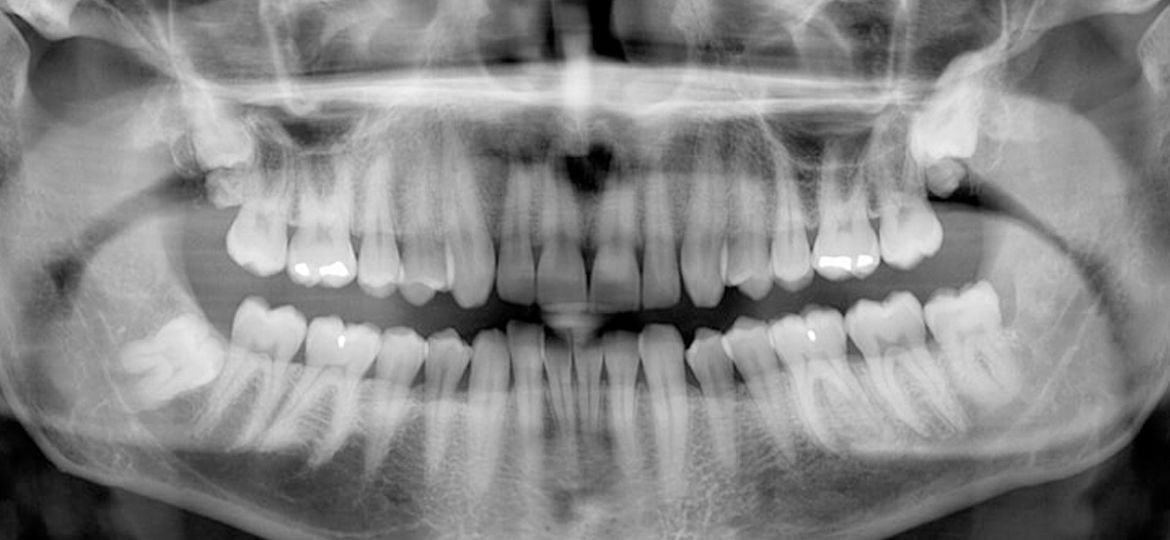

Panoramic X-rays show a broad view of the entire mouth, including all teeth, jaws, sinuses, and nasal area. They are useful for comprehensive evaluations and treatment planning.